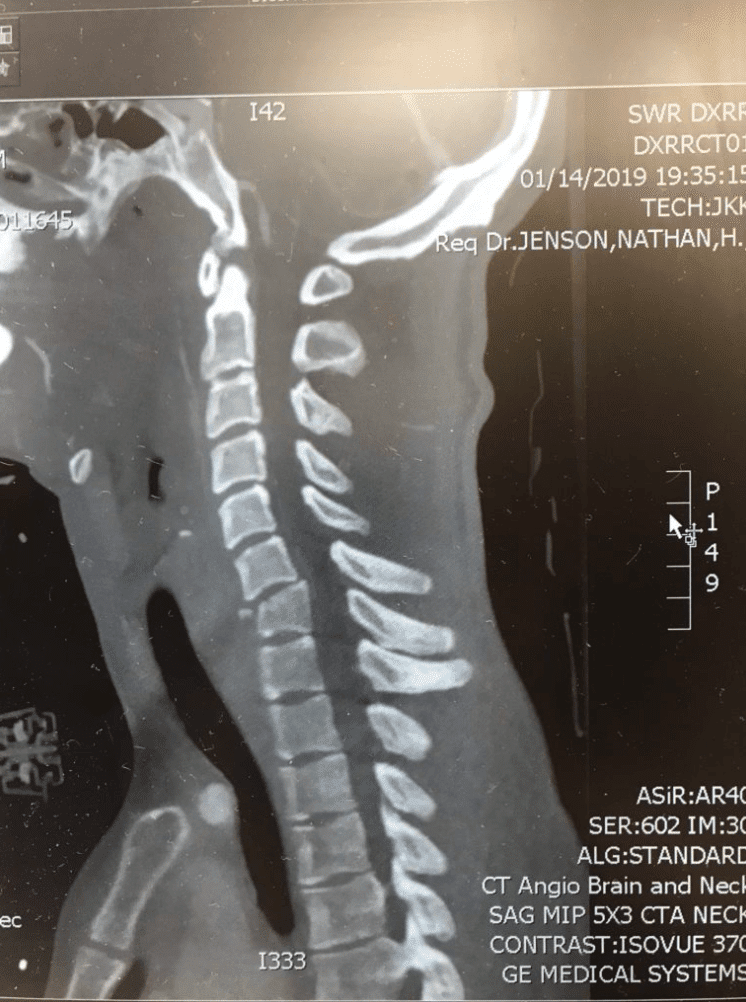

Earlier this month on January 14, 2019, Blake Savage crashed while riding at a private supercross track in Mesquite, Nevada, sustaining a cervical spinal cord injury due to fractures to his C6 and C7 vertebra. Savage was immediately transported to Dixie Regional Medical Center in St. George, Utah, where his injuries were assessed and a surgical plan was quickly put into place. On Tuesday, January 15, Savage underwent successful surgery, where doctors completed a C5 to T1 posterior spinal instrumentation and fusion, which addressed the fractures and stabilized the spine.